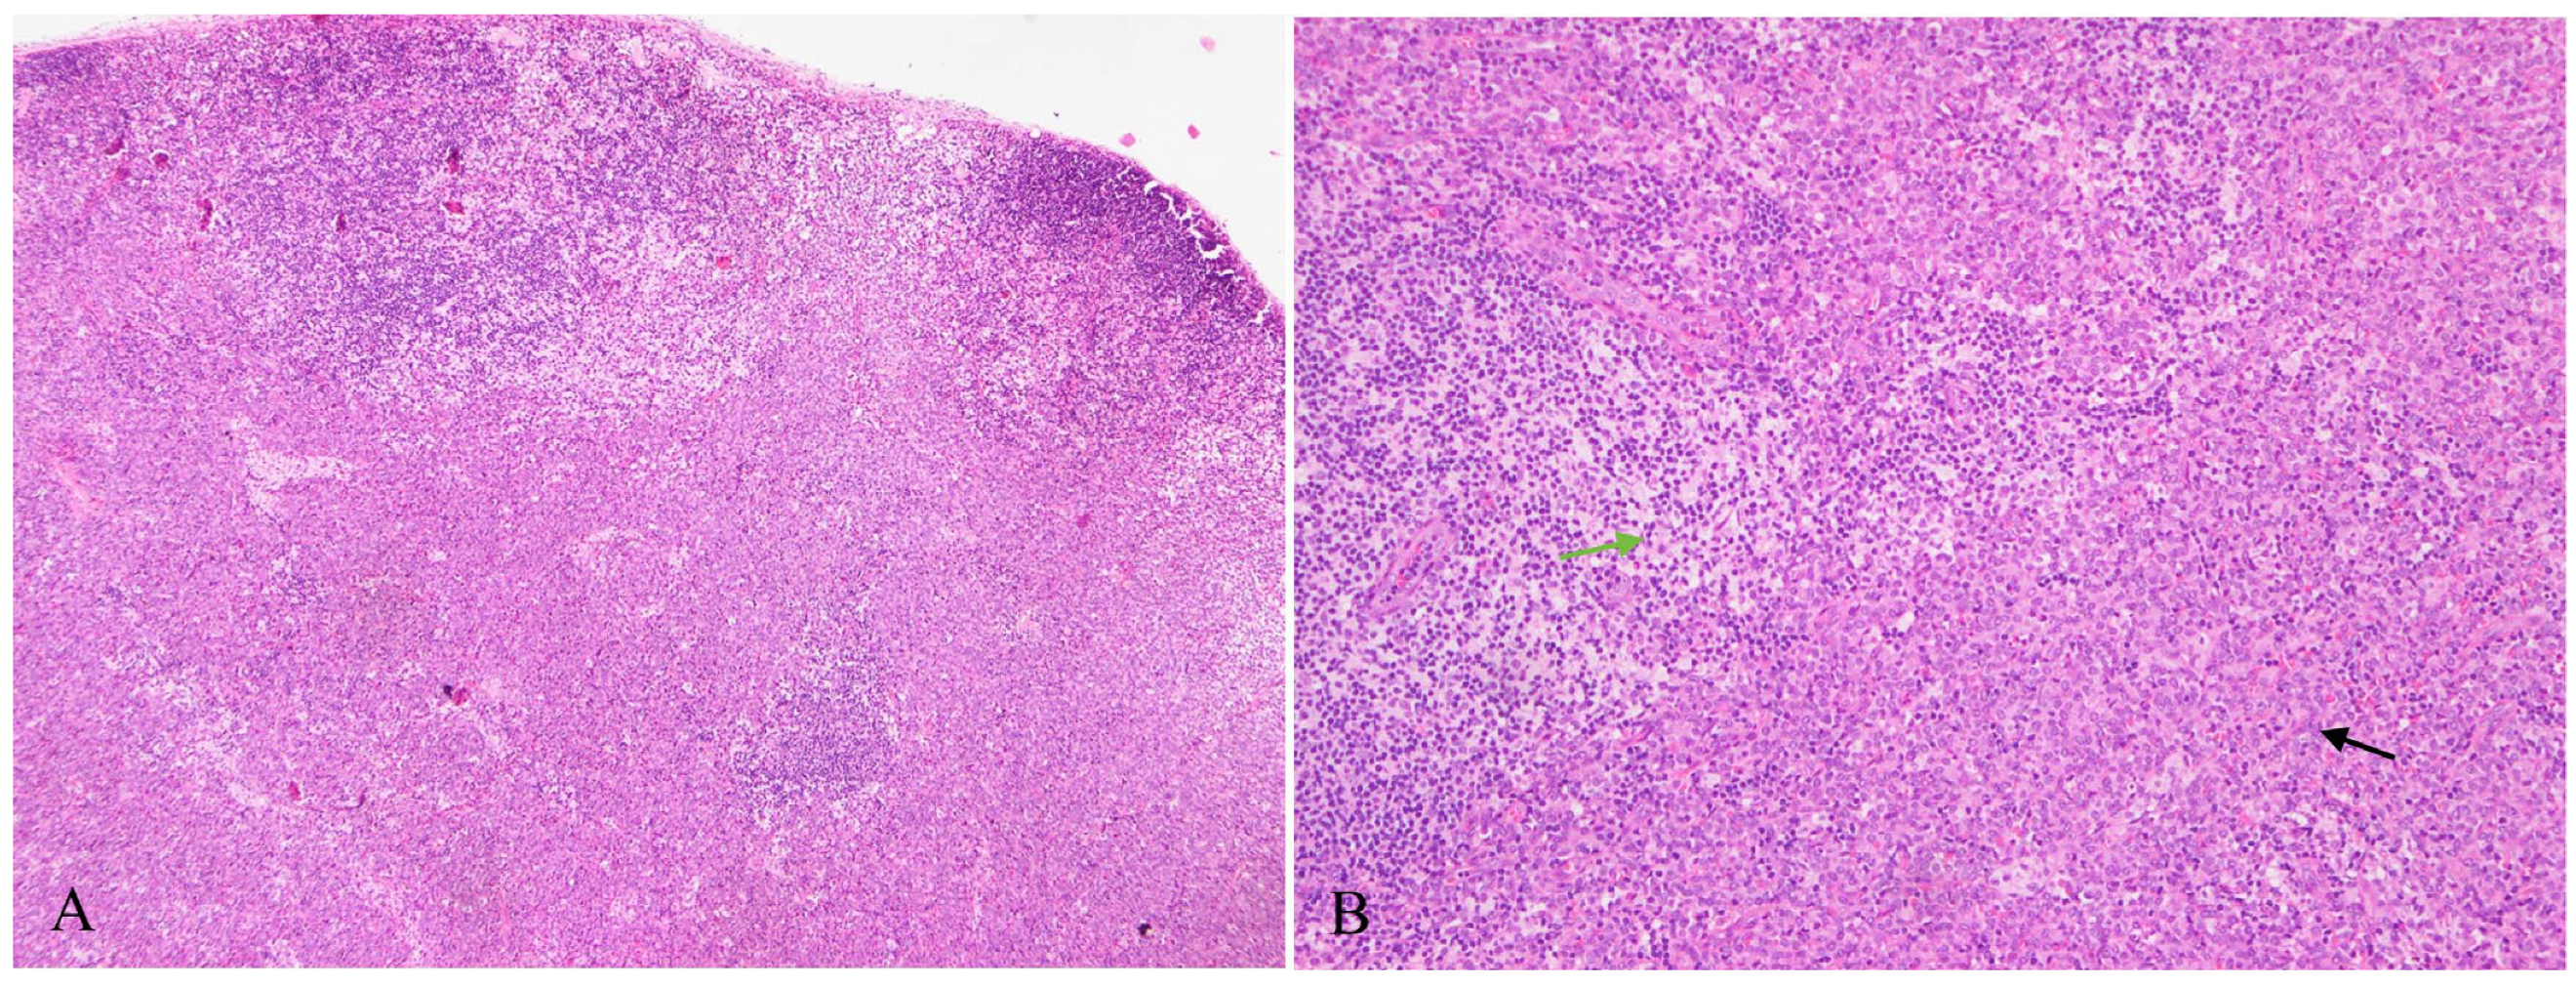

2. Case Presentation